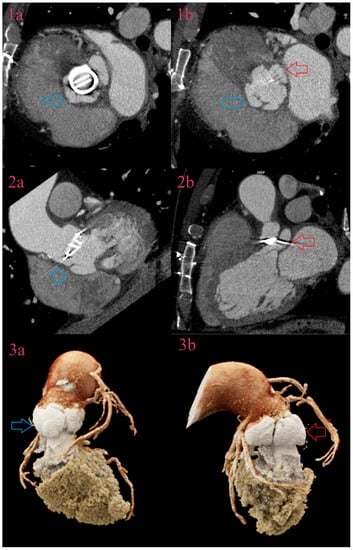

3.3. Vegetations

3.4. Aneurysms

3.5. Perforations